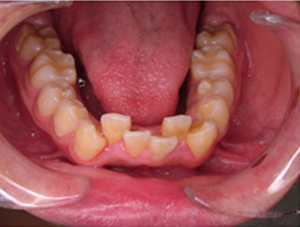

| 治療前 | ![]() |

治療後 |

![]() |